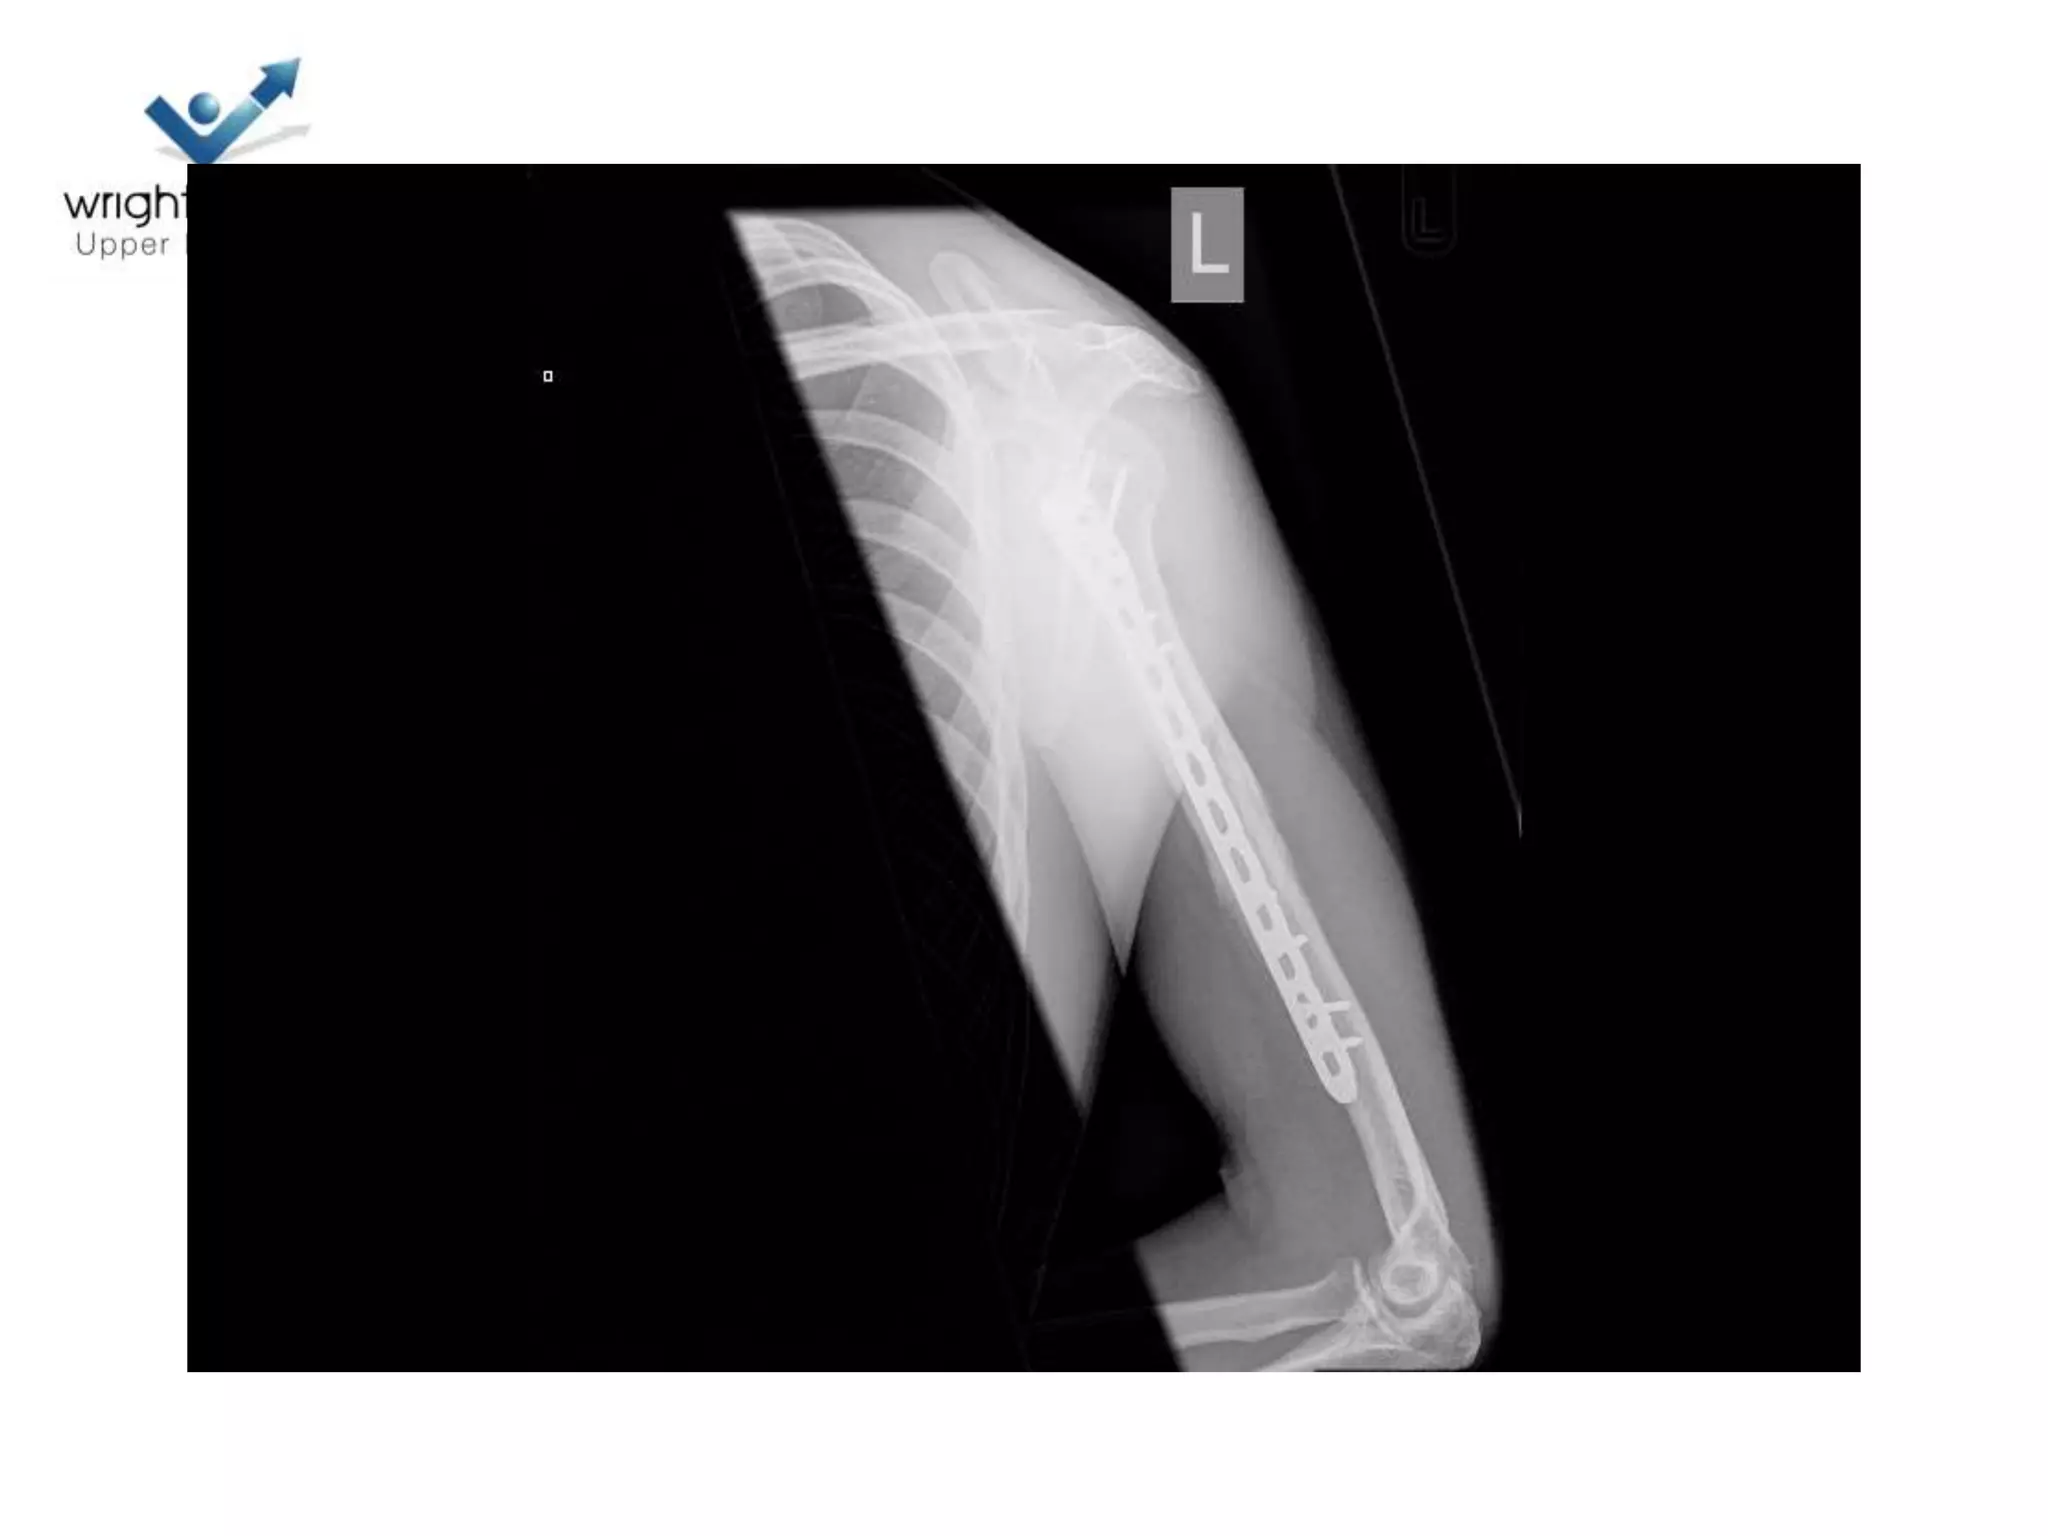

4 Next…

5 Next